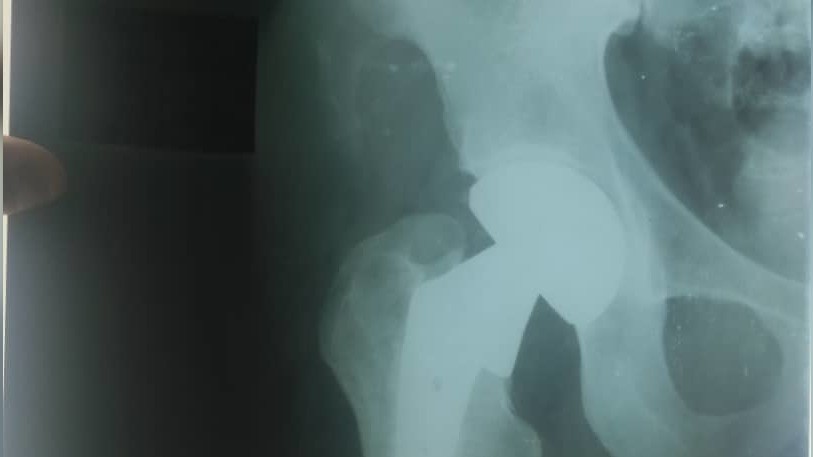

Токмокто жол кырсыгына кабылган 65 жаштагы кишиге оор операция жасалды